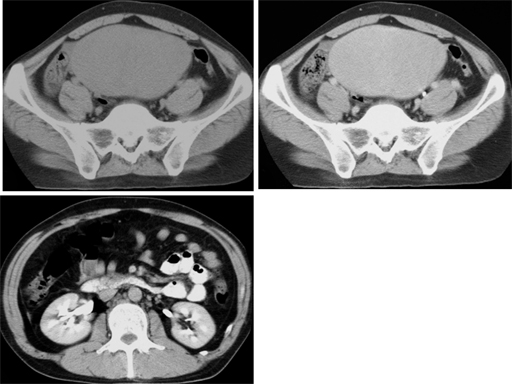

No.82症例6:35歳男性

1ヶ月前より下腹部の鈍重感。 腫瘤を触知していたが放置していた。

CRP2.7 WBC 8,800 ESR 65mm/1hr, 107mm/2hrs ALP 559 IU/l

• 図1 左上:非造影CT(骨盤レベル)/右上: 造影CT遅延相(骨盤レベル)/左下 造影CT遅延相(腎臓レベル)